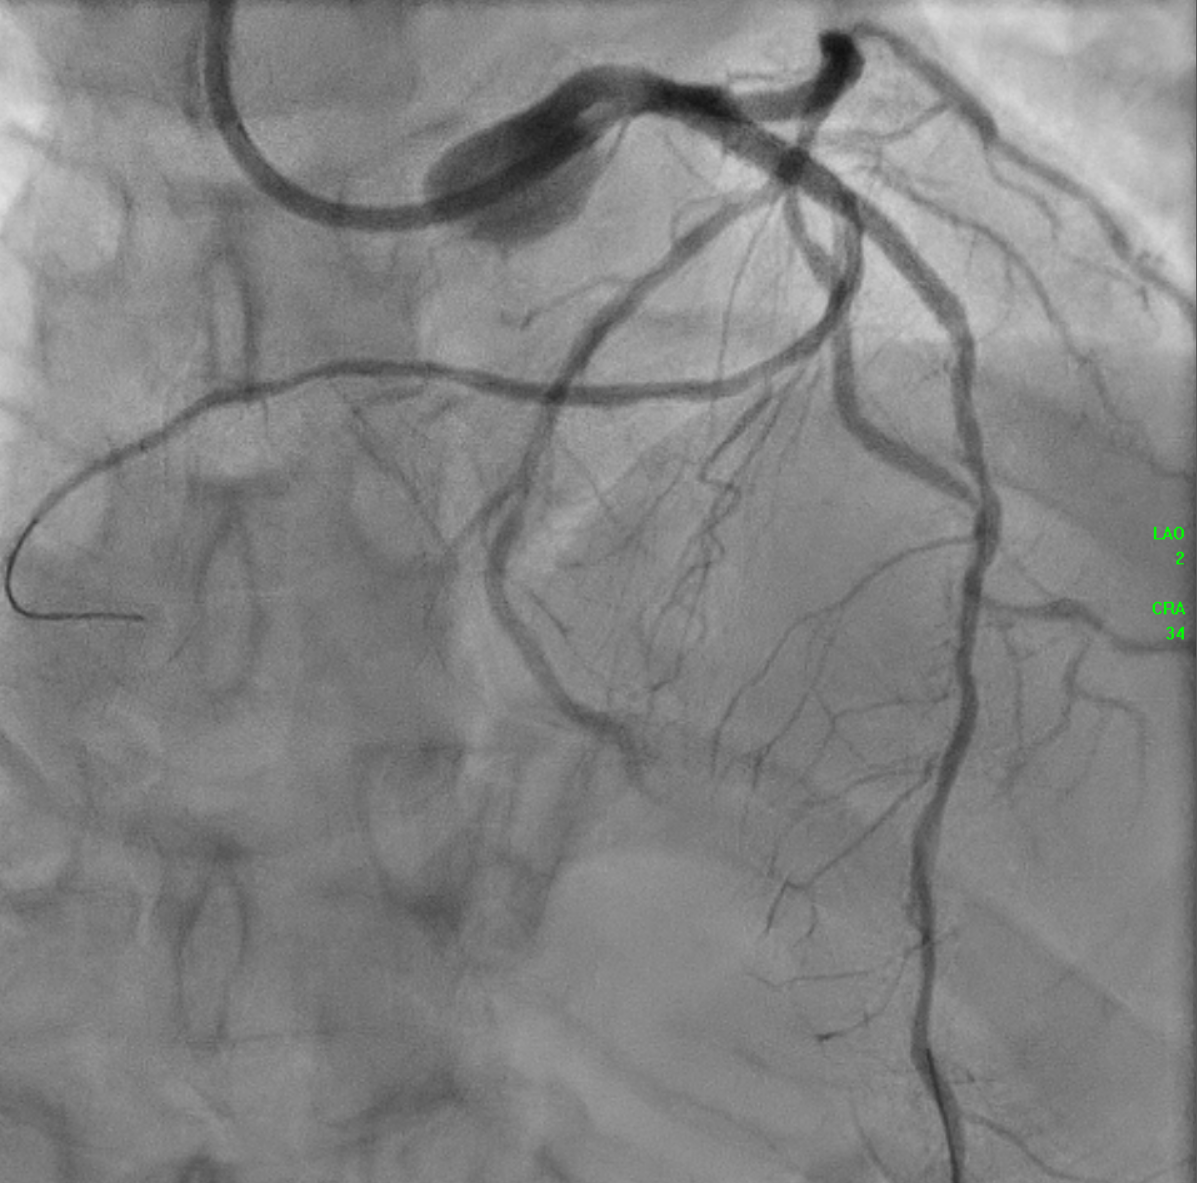

The initial angiogram on July 3rd, 2025, showed two-vessel coronary artery disease, with diffuse atherosclerosis extending from the proximal to distal LAD and moderate stenosis of the OM2. The RCA was absent and appeared to be supplied by the D1 branch, which showed severe disease at the ostium and mid segment. A repeat angiogram showed drop of blood flow with TIMI 2 flow to the distal LAD and RCAterritories. Then we proceed to PCI to LAD and RCA.

PA-CRA + SPIDER.mp4

An IVUS-guided PCI of the LAD and RCA was performed via right radial access. An EBU 3.5, 7 Fr guiding catheter engaged the left main, and a Sion Blue wire was advanced to the distal LAD for pre-dilatation with a 2.5 mm NC balloon. Wiring the anomalous RCA from the LAD was challenging due to a retroflexed ostium but was achieved using a reverse wire technique with adual-lumen (Sasuke) catheter and Sion Black wire. Difficulty crossing the mid RCA, likely due to dissection, required multiple wire exchanges before reaching the distal RCA. Lesion preparation used 2.0 mm and 1.5 mm NC balloons in the RCA. IVUS showed LAD diameters of 2.5mm distally with diffuse disease and < 40%plaque burden. A hybrid revascularization strategy was planned. Further preparation involved 3.0 mm and 2.0 mm balloons in the LAD and RCA. DCBs (2.0 ¡¿25 mm in distal LAD; 2.0 ¡¿ 20 mm in RCA) were applied for 60 seconds each. A Xience Sierra 3.0 ¡¿ 38 mm DES was deployed in the proximal–mid LAD,post-dilated with 3.0–3.5 mm NC balloons and optimized with a 4.0 mm POT. IVUS revealed a distal edge dissection, covered with an additional overlapping Xience Sierra 2.75 ¡¿ 23 mm DES. Final IVUS confirmed good stent expansion (MSA6 mm©÷), and angiography showed non–flow-limiting distal LAD dissection with TIMI 3 flow in both LAD and RCA.